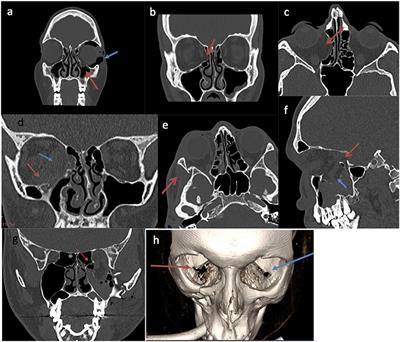

Frontiers A Functional Radiological And Soft Tissue Classification To Predict Outcomes In Orbital Fracture Surgery In A Multidisciplinary Real World Setting

Anatomic Factors Predicting Postoperative Strabismus In Orbital Wall Fracture Repair Scientific Reports